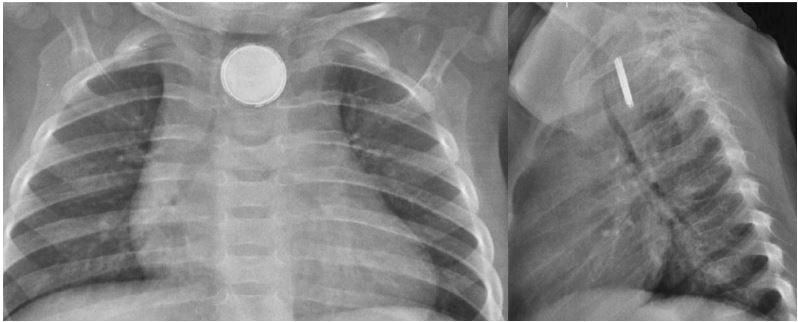

Menino, 2 a, é levado ao pronto-socorro com história de um episódio de vômito após engasgo enquanto brincava sem supervisão. No momento assintomático. Última mamadeira de 200 ml de leite há duas horas. O acompanhante acredita que faltam peças do brinquedo e que a criança pode ter ingerido algo. Radiograma de tórax:

A CONDUTA É: